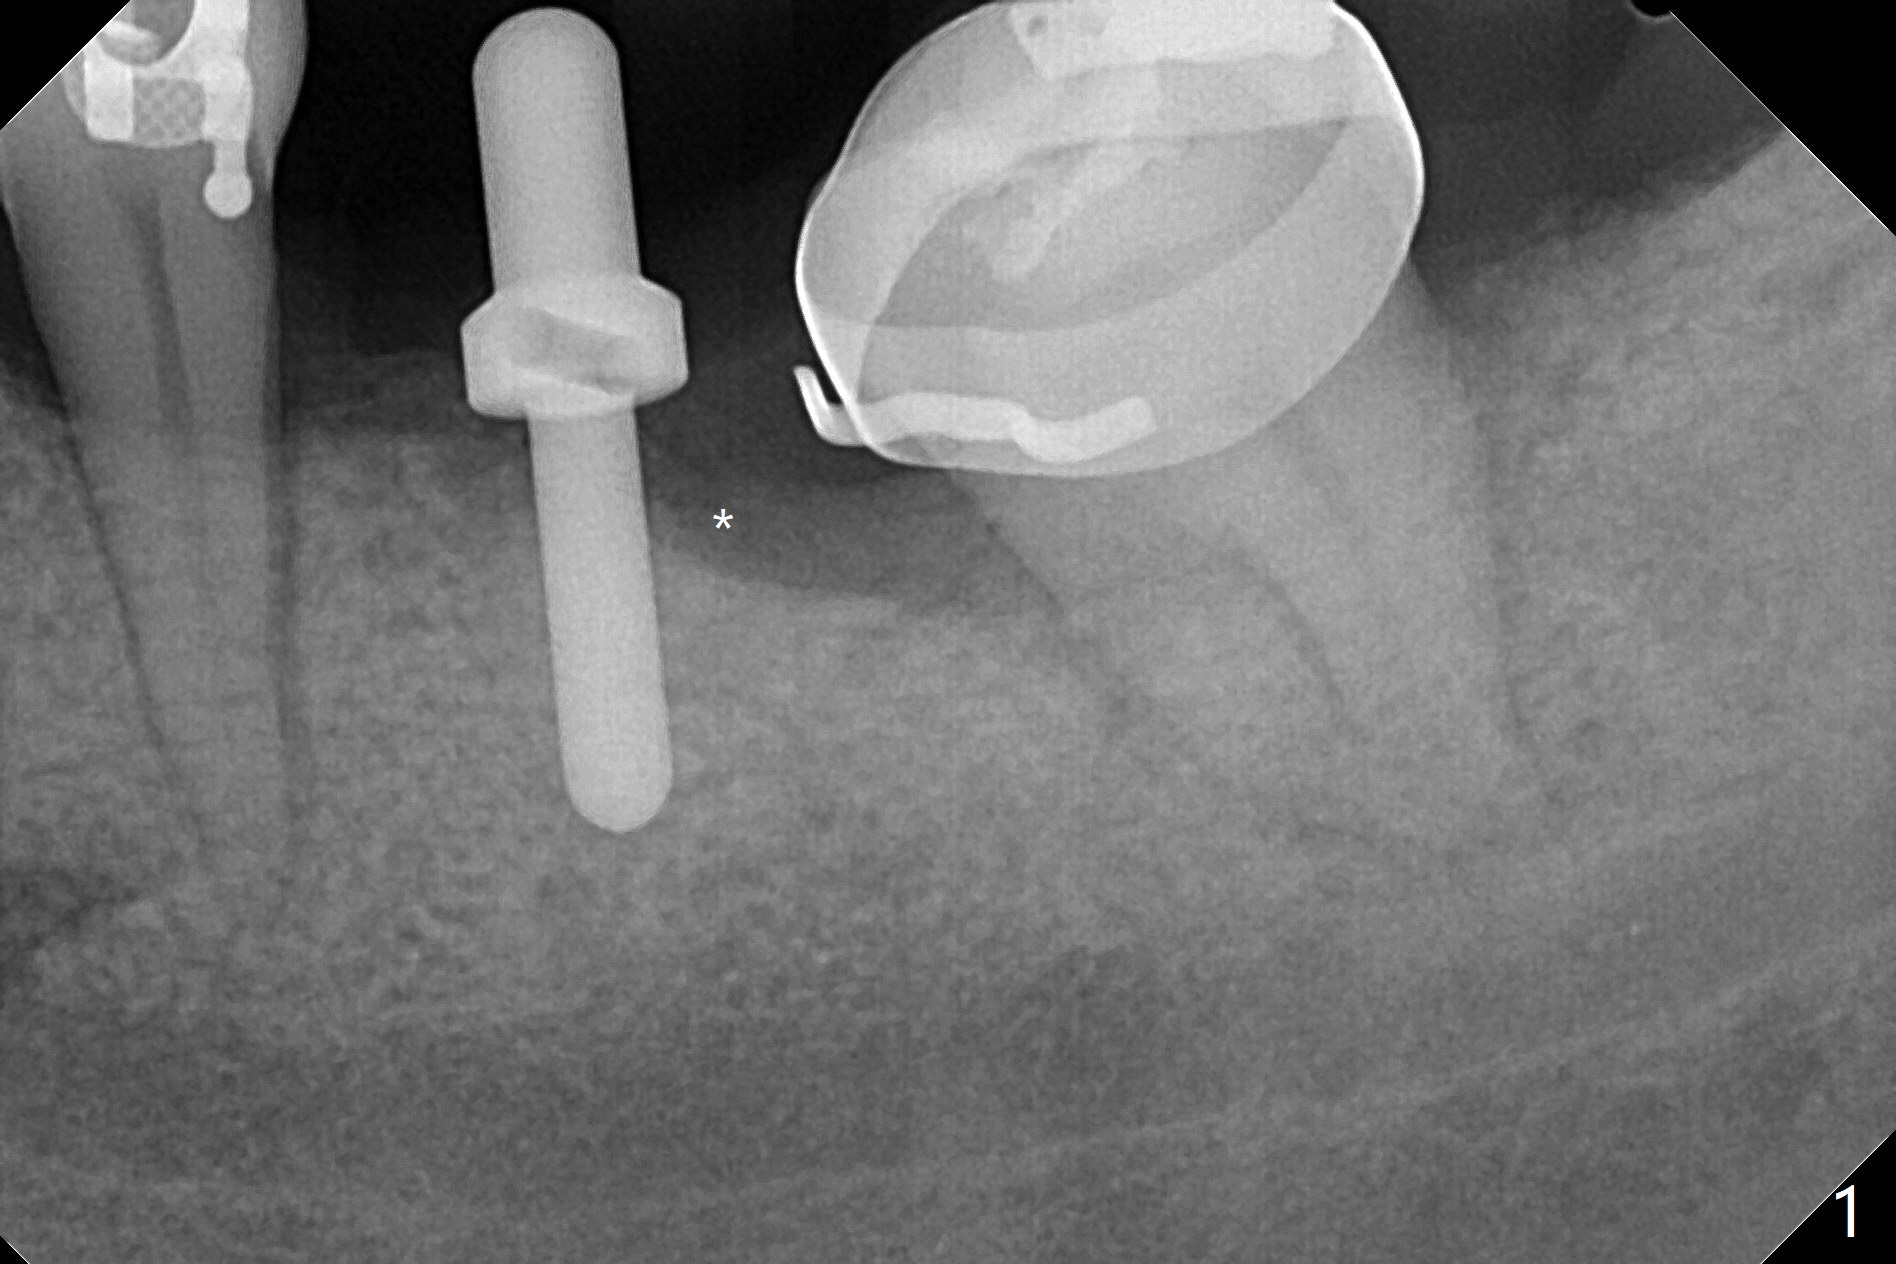

31岁女19号牙残根拔除,没有植骨,牙齿矫正创造了大约近远中10.5毫米空间,先锋钻深度8毫米(图一),远中舌侧骨质缺损(*)。使用4x7.3毫米钻头(实际长度8.5毫米)后,植入4.5x7.3毫米植体,远中大约3个螺纹暴露(图二)。使用4x8.5毫米钻头后,植体种深些(图三),但是根尖仍有空间(*)。再种深后(只有一个螺纹暴露),放置基台和粘性骨粉(图四:*),覆盖PRF,缝合,放置矫正钢丝和牙周敷料。